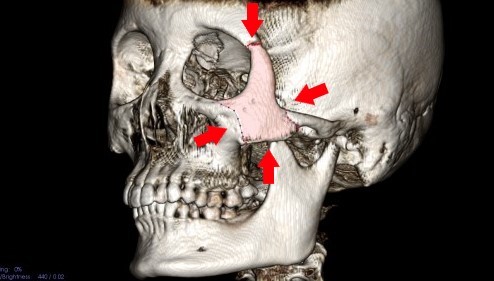

頬骨_痛い時_頬骨の高さの水平線

上のラインで、顔を輪切りにすると。

頬骨_痛い時_頬骨と上顎洞

CT像は、こうなります。

頬骨の裏には、

上顎洞という空洞(副鼻腔)があります。

頬骨が痛い事は、

上顎洞炎(副鼻腔炎)と、

関係が近いと言えます。